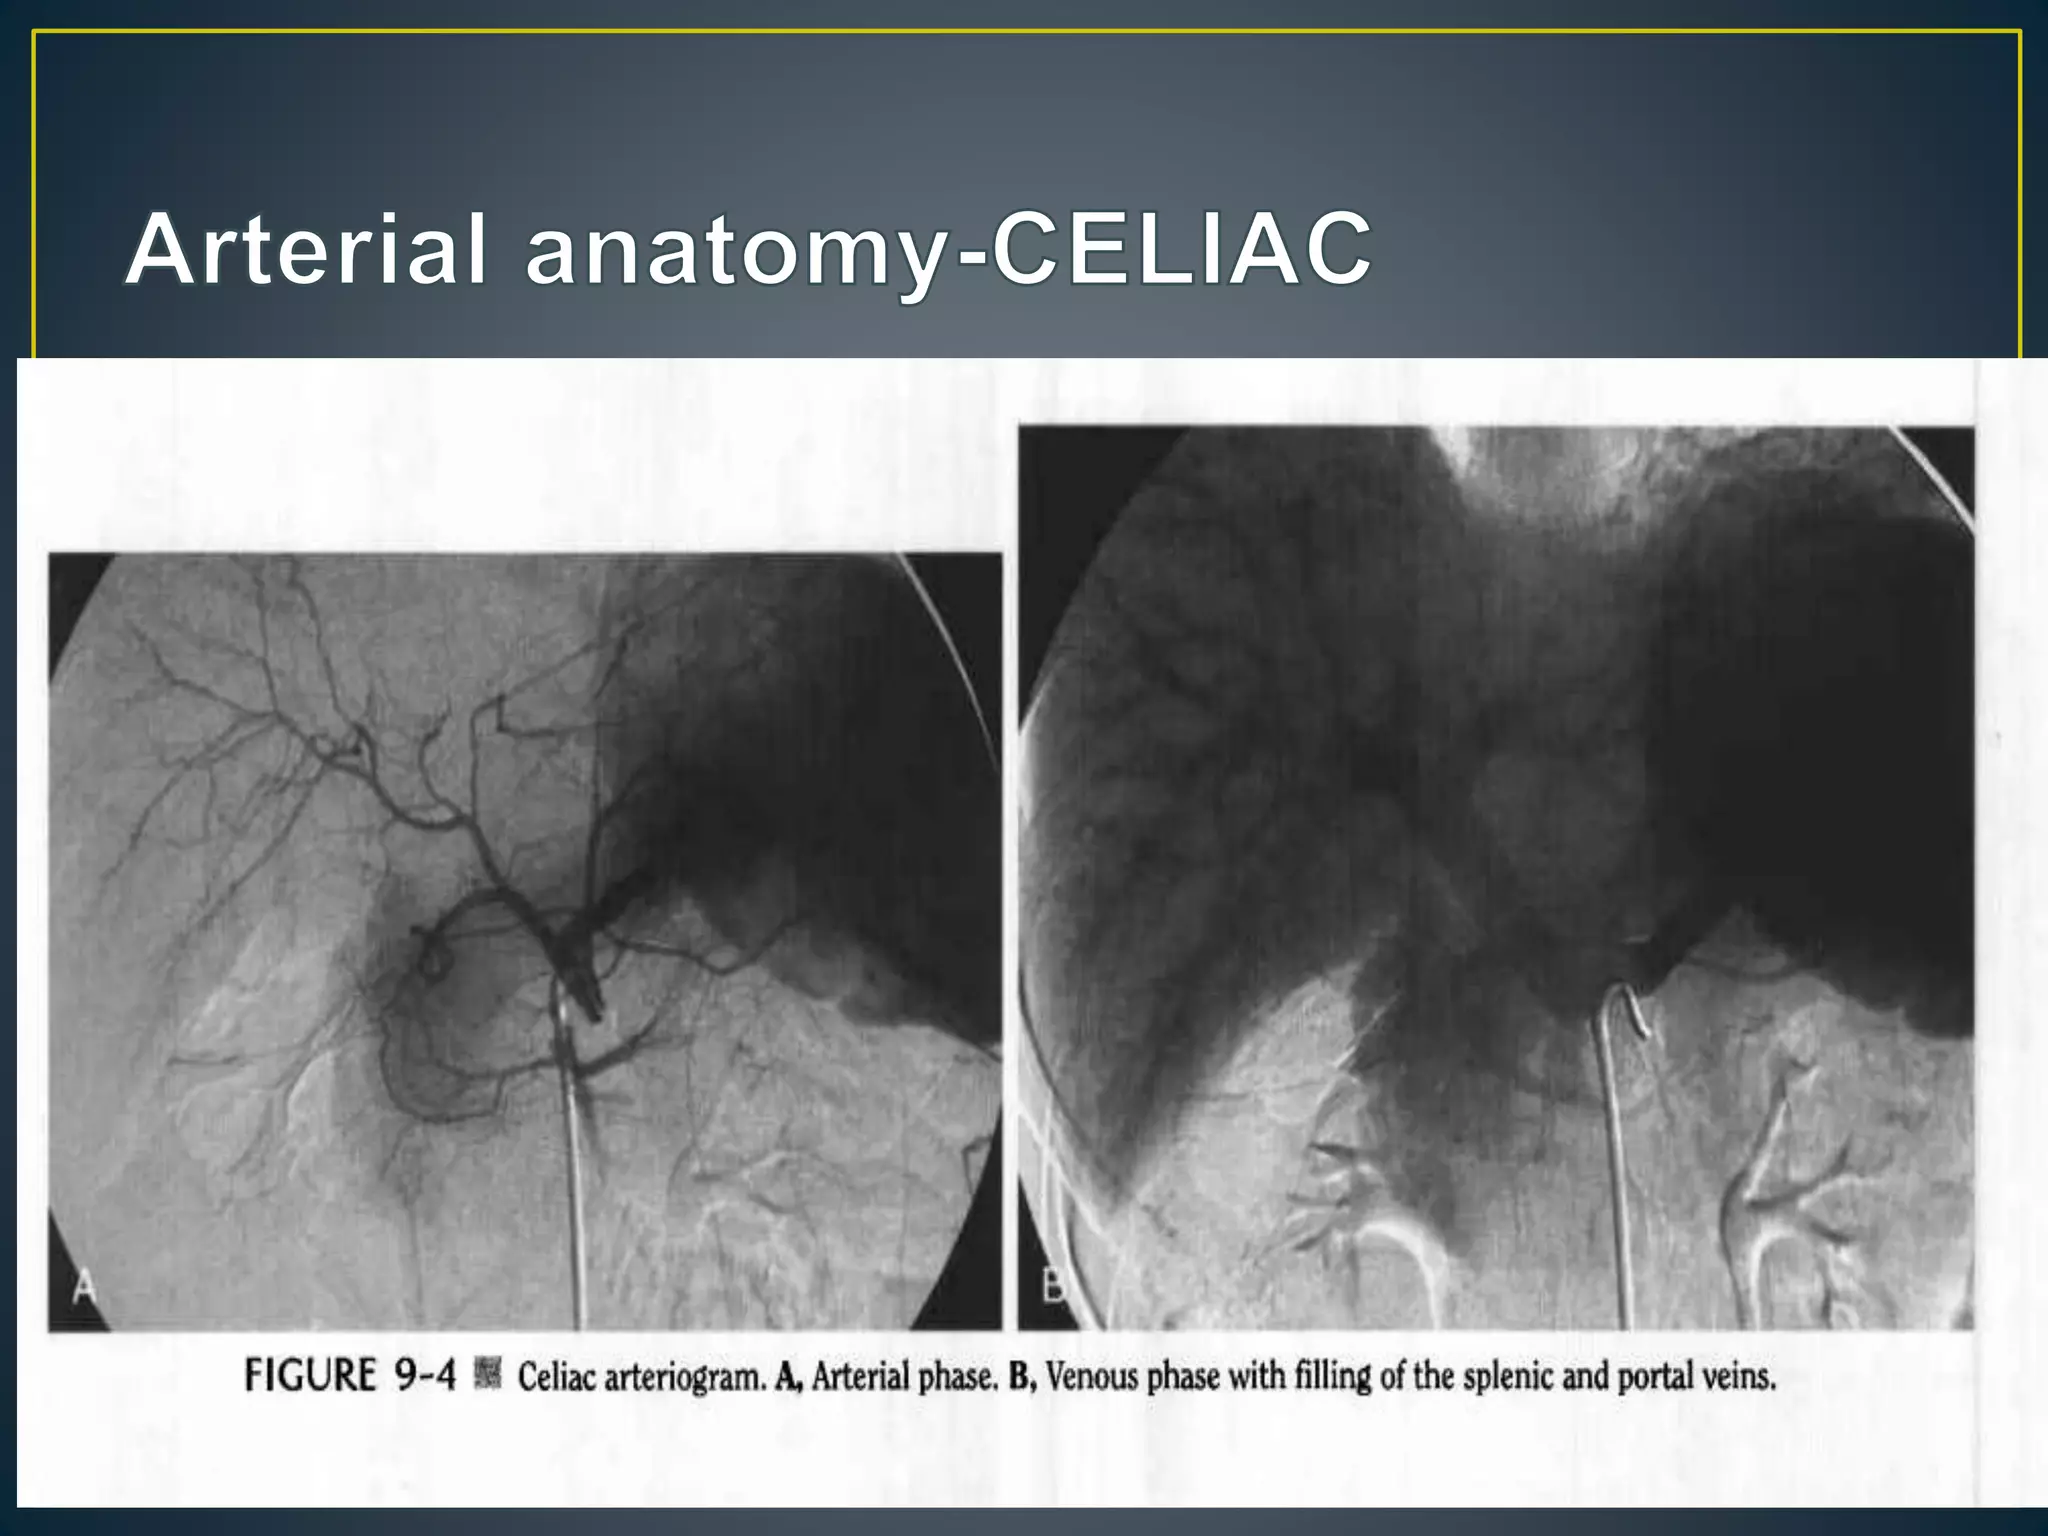

• The celiac artery originates from the anterior surface of

the aorta at about the T12 level .

• The main trunk can take an upward, downward, or

forward course. Within 1 to 2 cm of its origin, it gives off

the left gastric artery and then divides into the common

hepatic and splenic artery

• The common hepatic artery runs toward the liver. After

giving off the gastroduodenal artery, it becomes the

proper hepatic artery and then divides into right and left

(and occasionally middle) hepatic arteries

• The middle hepatic artery supplies the quadrate lobe.

• The right gastric artery usually takes off from the

common or left hepatic artery but often is not visualized

at angiography. It supplies the pylorus and the lesser

curvature of the stomach and communicates with

distal branches of the left gastric artery.

• The cystic artery usually originates from the right hepatic

artery, although it may arise more proximally.